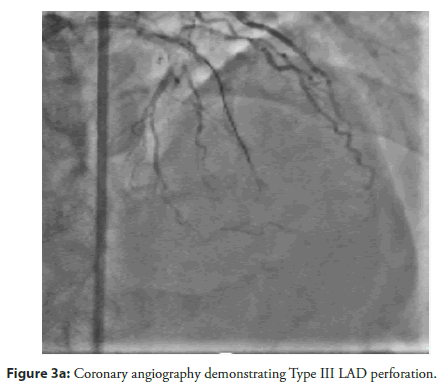

The patient and his family declined Coronary Artery Bypass Graft (CABG) surgery; therefore, the primary treatment strategy was to attempt revascularization of the LAD CTO lesion. An antegrade approach was selected, with the right femoral artery used as the primary access route and the right radial artery used for additional support. The initial attempts were made using Fielder XT, Fielder XT-R, and Gaia Next 2 guide wires (Figure 2a–Figure 2c). However, the Caravel microcatheter could not be advanced across the tight lesion. Therefore, predilatation was attempted using a 1.25 × 10 mm balloon followed by a 2 × 12 mm Non-Compliant (NC) balloon. Unfortunately, the wire was found to be in a false tract, which resulted in a Type III LAD perforation with subsequent cardiac tamponade. Emergency pericardiocentesis was performed (Figure 3a, Figure 3b). The LAD perforation was successfully sealed using 2 mm and 3 mm Hilal coils (Figure 4a–Figure 4c).

Figure 3a: Coronary angiography demonstrating Type III LAD perforation.